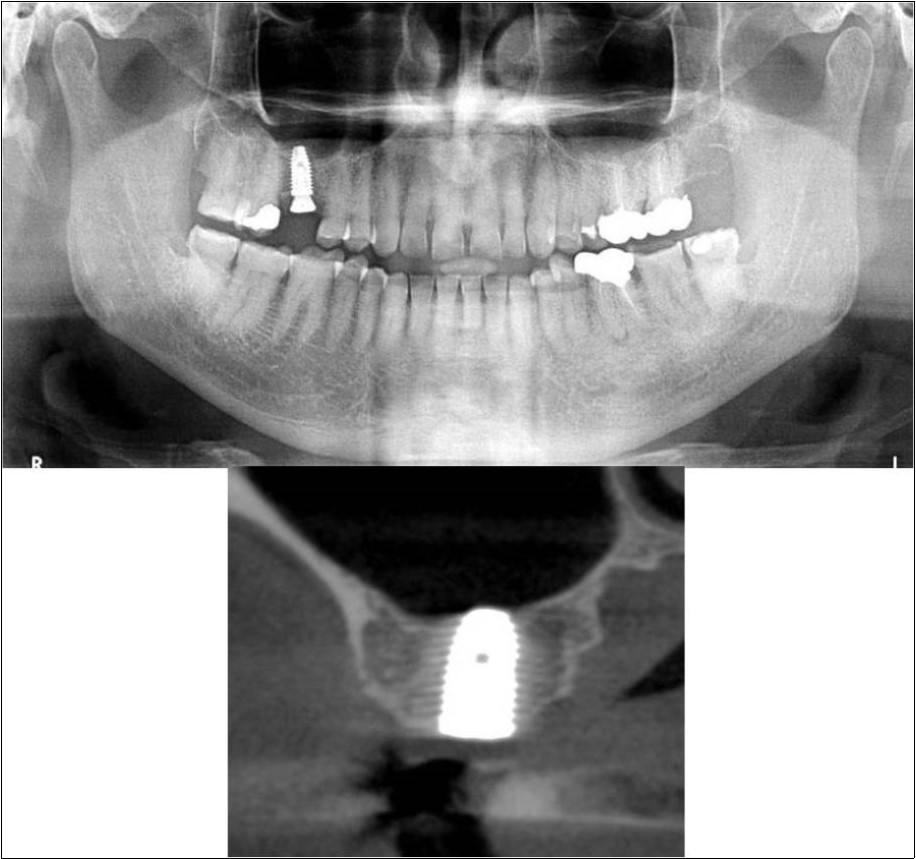

Patient underwent the procedure of indirect sinus elevation using sinus osteotomes in relation to 17 region. Calcium phosphosilicate putty was dispensed as the graft material through the crestal osteotomy site to maintain the elevated sinus membrane followed by placement of a dental implant measuring 5 x 10mm under local anaesthesia and strict aseptic protocols .The implant was allowed to osseo-integrate for a period of six months during which the patient was followed-up periodically and was assessed for peri-implantitis, crestal bone loss and mobility. At the end of 6 months, a repeat CBCT scan was advised to evaluate the increase in bone height. (Figure 9a,b, pre-treatment; Figure 10a,b, post-treatment)

Figure 9.(a,b) Pre-treatment OPG and cross section of CBCT showing residual alveolar bone height for Case No.2

Figure 10.(a,b) Post-treatment OPG and cross section of CBCT showing residual alveolar bone height for Case No.2